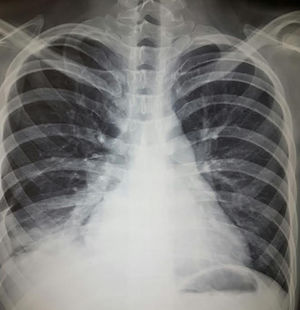

Pronóstico. Las series antiguas reportan una mortalidad de hasta el 50%; la serie más reciente reportó una mortalidad del 40%28. Si bien es una complicación poco común, la neumonitis lúpica durante el embarazo y en el postparto se ha asociado a desenlaces particularmente adversos29-31. El predominio de linfocitos en LBAV se asocia a evolución más favorable, mientras que el predominio de eosinófilos o neutrófilos se asocia a mayor mortalidad. Hasta en el 50% de los supervivientes persisten los infiltrados intersticiales y función respiratoria anormal con riesgo de progresión a neumonitis crónica intersticial3,14. En la figura 3 se muestran datos de neumonitis e hipertensión pulmonar.

Hombre de 22 años con hermano gemelo con lupus eritematoso sistémico, ambos con datos de síndrome de Schnitzler (cuadros intermitentes de fiebre, urticaria, dolor abdominal, angioedema, artritis), en los últimos 2 meses con disnea progresiva hasta la de mínimos, poliartritis, hipertensión, edema mecánico y en los días precedentes tos e incremento de disnea. A la exploración, con complejo de la pulmonar de Chávez y síndrome de condensación basal derecho; radiografía con datos de hipertensión pulmonar, 4 arcos, neumonitis basal derecha y derrame homolateral. Se realizó diagnóstico de neumonitis lúpica que se manejó con prednisona 0,5mg/kg/día y ciclofosfamida con adecuada respuesta.